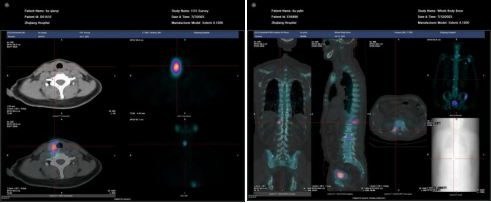

前列腺癌治疗后复发:18F-PSMA PET/CT显像示前列腺癌去势治疗术后复发并骶尾椎骨转移瘤。

3.4肿瘤分期对比

图A 图B

A、B两图均为左肺周围型肺癌,病灶大小相似,A未见远处转移病灶,B全身广泛转移,临床分期分别为ⅡB期及ⅣB期,PET/CT不同分期影响临床治疗决策。